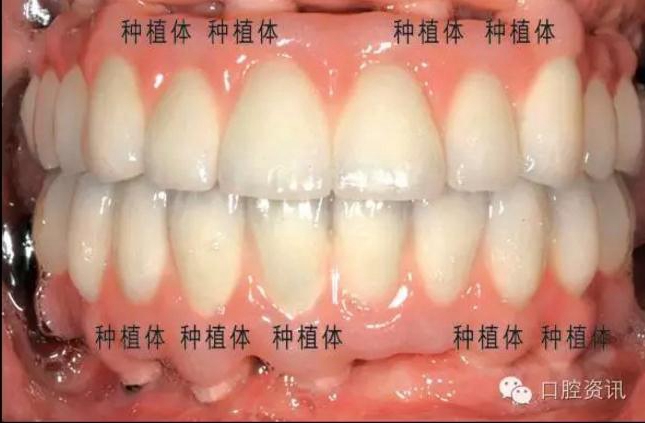

17.jpg

圖 17. 種植牙修復(fù)單顆前牙缺失

18.jpg

圖18. 種植牙修復(fù)上下頜全口牙缺失